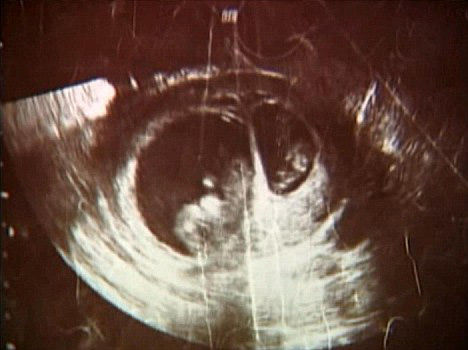

حالة نادرة لأمريكية.. "حمل خلال الحمل"!!

فاجأت امرأة من ولاية أركنساس الأميركية الأطباء بعد أن تبين أنها حامل بطفلين ليسا توأما. وكشفت شبكة "أي بي سي" الأميركية أنه بينما كان الأطباء يجرون صورة صوتية لجنين تود وجوليا غروفنبرغ الذي تبين أنه فتاة سيدعونها جيليان، اكتشفوا جنيناً آخر أصغر ينمو إلى جانبها.

وأشار الأطباء إلى إمكانية أن تكون جوليا قد حملت بطفل آخر بعد أسبوعين ونصف من حملها بجيليان. وقالت الطبيبة كارين بويل من مركز بالتيمور الطبي، في مقابلة مع برنامج على قناة "أي بي سي" إن التقارير الواردة حول حمل جديد خلال الحمل الأساسي قليلة جداً، إذ لم تتمكن من إيجاد أكثر من 10 حالات.

في حين أشار طبيب جوليا إلى إمكانية أن تكون هذه حالة نادرة من "الحمل خلال الحمل" بسبب الفرق في حجم الجنينين، غير أنه أفاد بأنه لا يمكن التأكد من ذلك قبل ولادة الطفلين وإجراء تحاليل الكروموزم.

وفي حال ثبت أن الحالة التي تعاني منها جوليا هي حالة نادرة من "الحمل خلال الحمل" فسيولد كلّ من الطفلين في أوقات مختلفة، إذ قد تولد جيليان في نهاية العام 2009 بينما يولد شقيقها في بداية العام 2010.